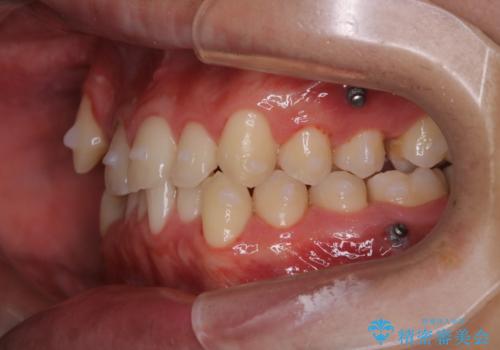

- マウスピース矯正中に、口臭が気になりクリーニングを行いたいとのことでした。染め出しをしての歯ブラシ指導とPMTC60分コースを行いました。

染め出し液を使ってプラークを染め出すことにより、普段の歯みがきで磨き残している場所を目で確かめることができます。